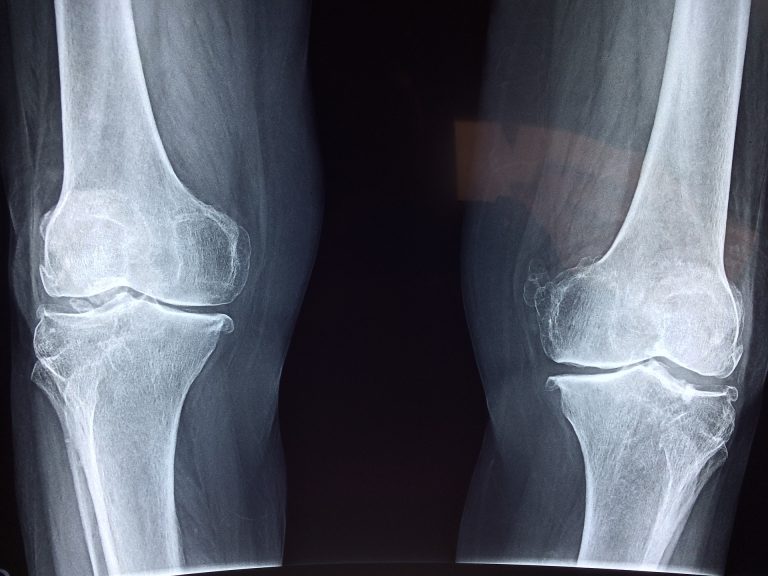

Piedi piatti: causa, conseguenze sulla postura e rimedi

I piedi piatti sono una condizione che può essere causa di fastidi come il dolore a cosce, ginocchia e caviglie. Ma può anche essere conseguenza di disturbi precedenti come la debolezza muscolare. Scopri quali possono esserei le cause scatenanti e i possibili rimedi.